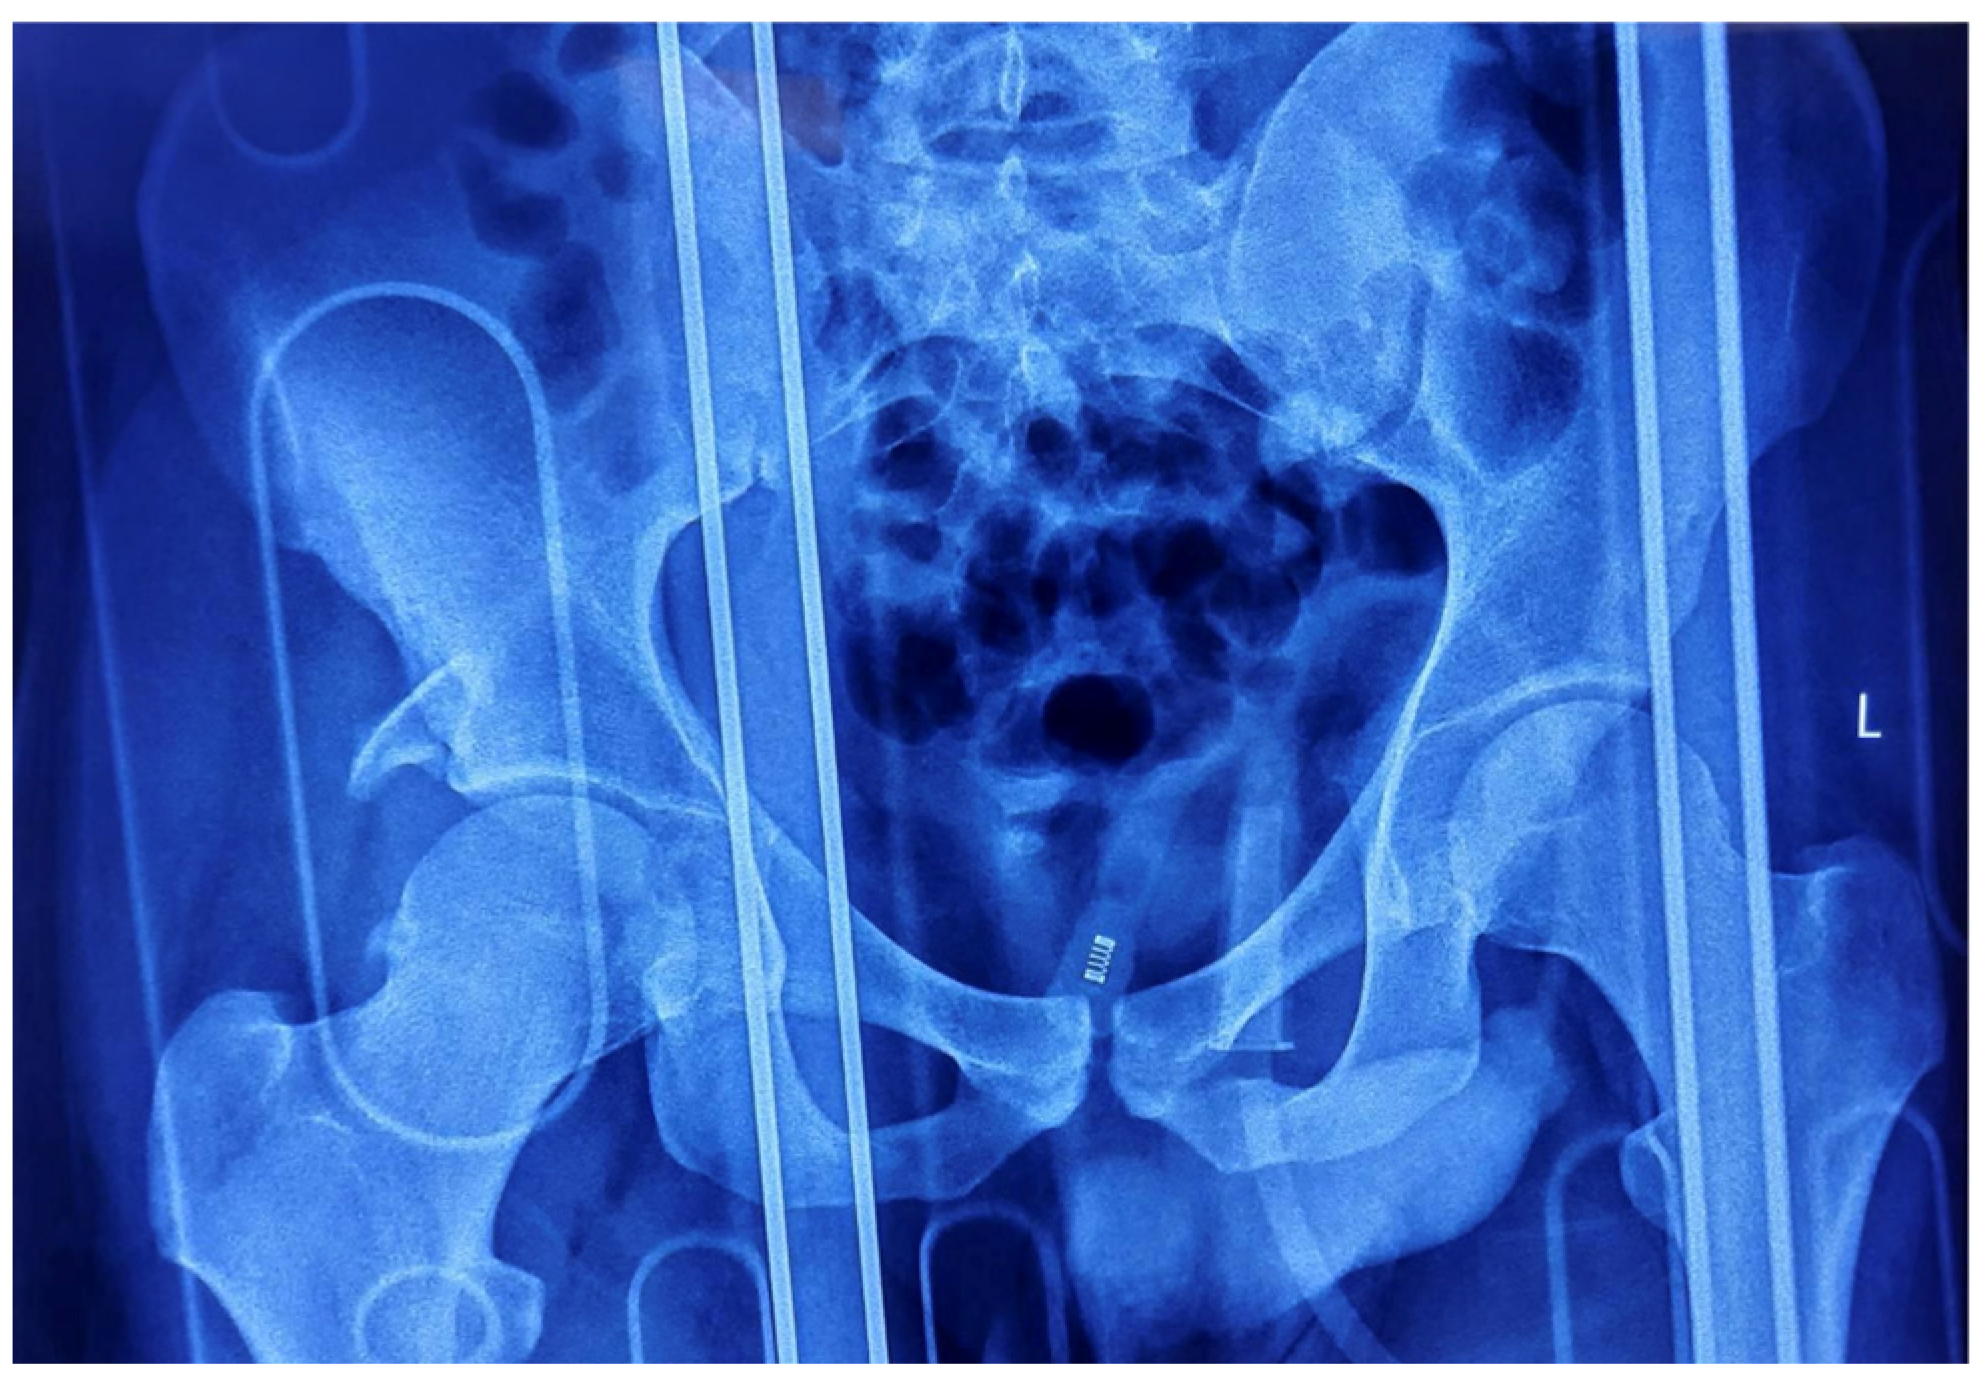

The patient underwent closed reduction under general anesthesia within two hours post-injury using fluoroscopic guidance. The Allis maneuver was employed for the right posterior dislocation, and the Captain Morgan maneuver was utilized for the left anterior dislocation, achieving concentric reduction on both sides. Post-reduction radiography confirmed joint congruity, but the right posterior acetabular wall fracture remained unstable, necessitating operative intervention (Figure 3).

Figure 3. Post-reduction AP radiograph of the pelvis showing joint congruity, as well as the right posterior acetabular wall fracture.